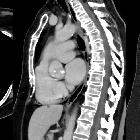

Sternale

Metastase im Manubrium mit Weichteilanteil bei Adenokarzinom des Ovars.